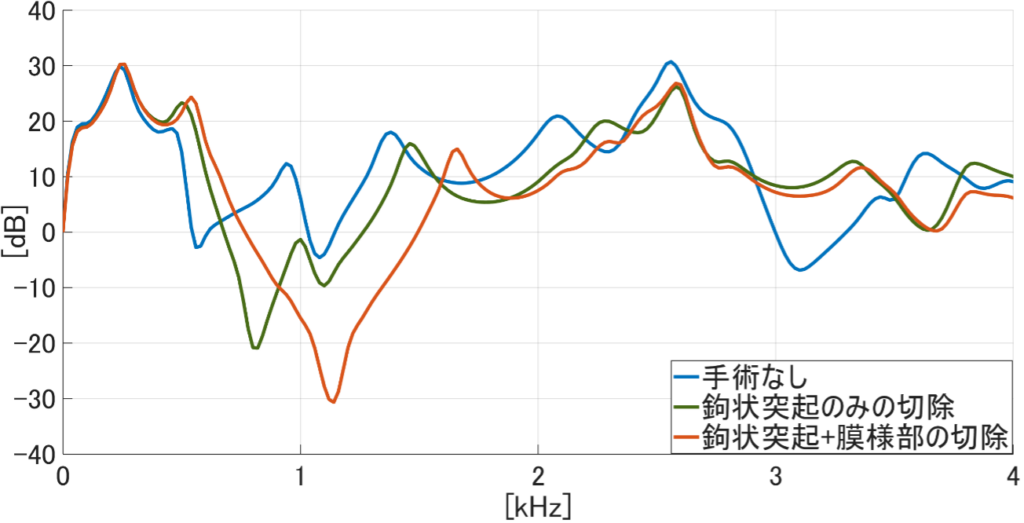

模擬手術と音響シミュレーションによる鼻副鼻腔の音響特性の解明について、現在は副鼻腔の部位の1つである上顎洞の開放範囲(切除規模)の違いによる音声変化への影響の検討に取り組んでいます。本研究室では患者のCT(Computed Tomography)データから鼻副鼻腔を含めた声道形状を抽出し、抽出したデータを用いて手術(模擬手術)を行います。そのデータに対して音響シミュレーションを用いることで、手術後の音声変化を予測する手法を確立しました。この手法の確立によって実際に実験を行うことが難しい、開放範囲の違いによる音声変化の違いを検討することが可能となりました。

そこで現在は、2024年度の研究にて副鼻腔のうち特に音声変化への影響が大きいことが示された上顎洞の開放範囲による音声変化について検討をしました。上顎洞の開放範囲は鉤状突起と膜様部の切除規模によって決まります。鉤状突起とは骨の突出部のことであり、膜様部は鉤状突起と接続している薄い粘膜のことです。これらの部位の切除によって副鼻腔の容積が拡大します。検討の結果として、上顎洞の開放範囲が小さい程音声変化が小さく、範囲が大きい程音声変化が大きくなる可能性が示唆されました。しかし、被験者によっては開放範囲が小さいのにも関わらず音声変化が大きくなる傾向も見られました。